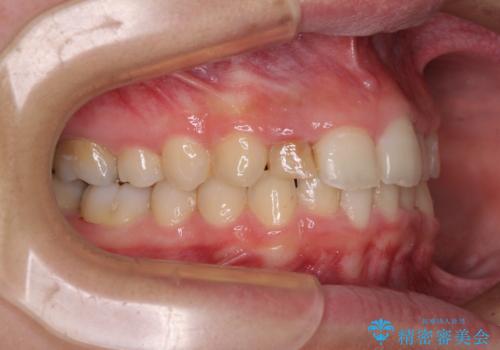

- 前歯の歯並びと不自然な色をした前歯のクラウンを気にして来院された患者様です。

上下前歯の歯列不正はインビザラインにより歯列を整え、その後に、前歯をオーダーメイドタイプのオールセラミッククラウンにて補綴治療することとしました。

前歯のデコボコを一番気にしていらっしゃいましたが、矯正治療により下顎前歯が隠れるほどのディープバイトも一緒に改善され、奥歯に負担のかかりにくい咬み合わせとなりました。